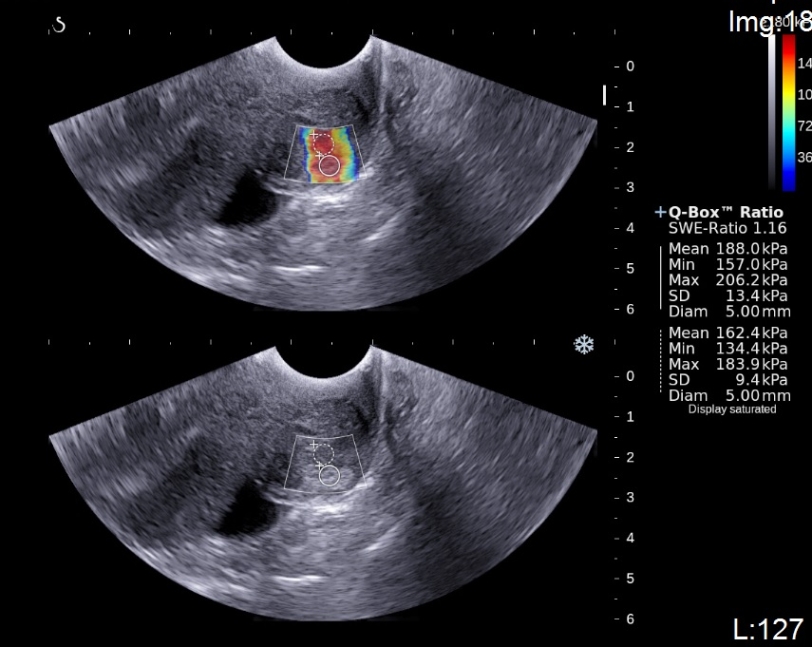

Пациентка 27 лет, 3 беременности. Последние роды 2 года назад, закончила грудное вскармливание год назад. В 3м триместре последней беременности в правой МЖ определялось плотное болезненное образование, которое увеличилось в размере к моменту родов. Пациентка проживала на тот момент в Морокко – данны...

Результаты выполненного исследования дают основание подтвердить выдвинутую гипотезу о том, что вариабельность занижает величину пороговых значений упругости печени и указывают на необходимость их пересмотра